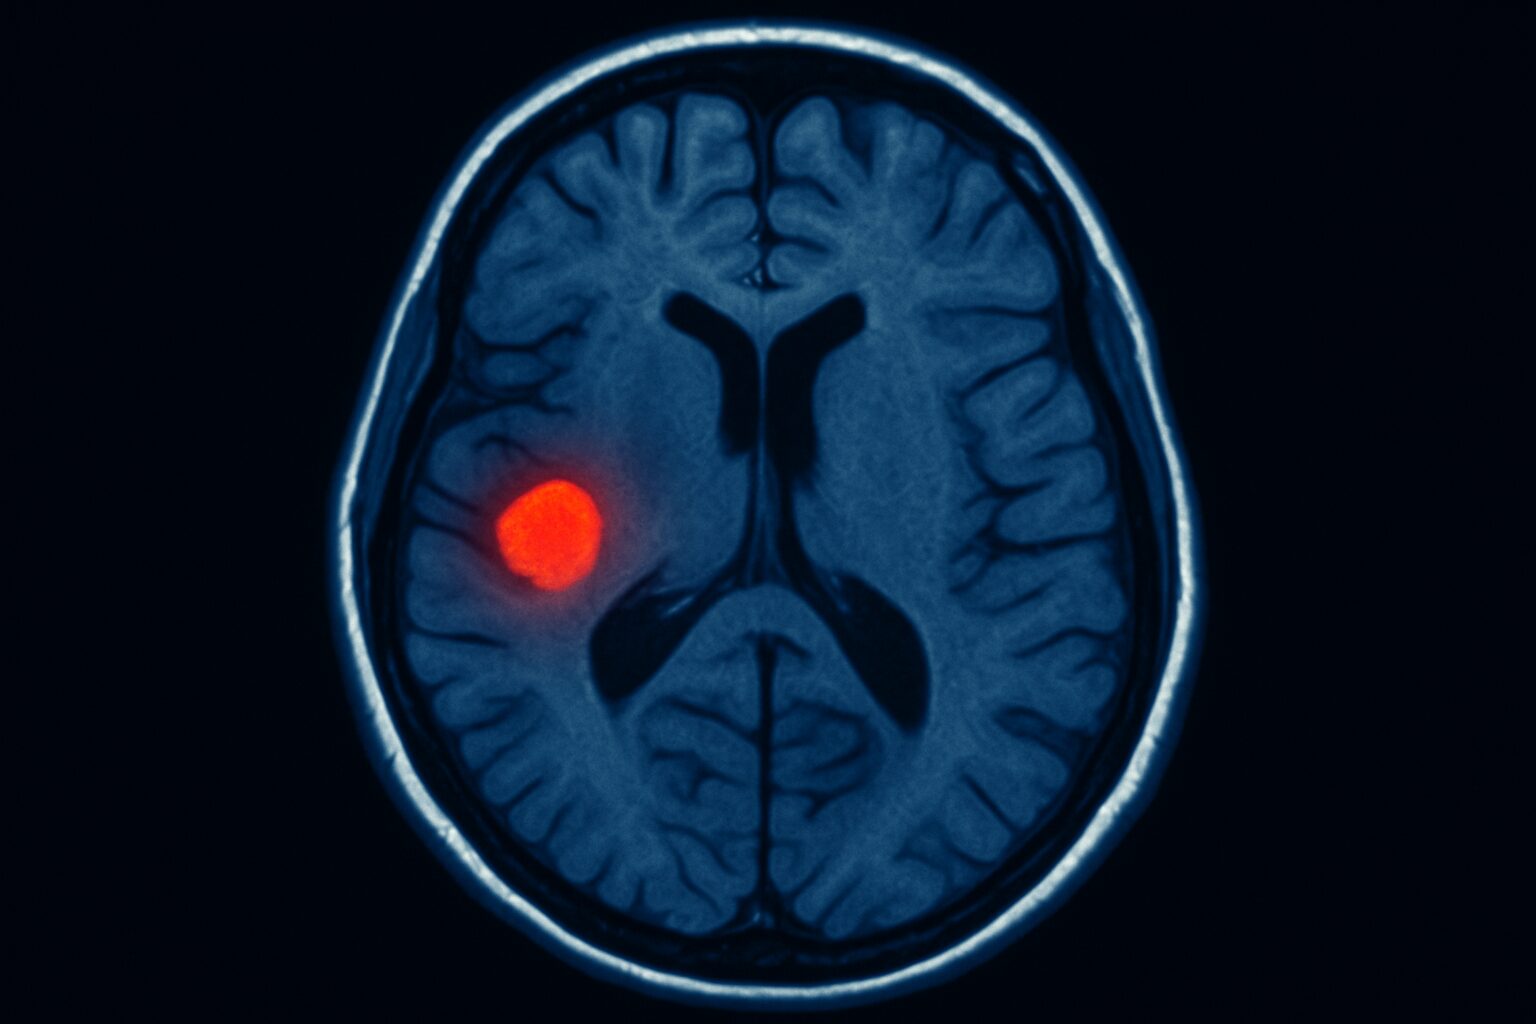

كشف فريق بحثي من مستشفى ملبورن الملكي للأطفال، بقيادة طبيبة الأعصاب “إيما ماكدونالد-لورز”، عن تطوير أداة مدعومة بالذكاء الاصطناعي قادرة على اكتشاف آفات دماغية دقيقة جدًا بحجم حبة التوت أو أصغر، غالبًا ما تفشل تقنيات التصوير التقليدية مثل الرنين المغناطيسي في رصدها. ويعد هذا الابتكار خطوة ثورية قد تغيّر حياة آلاف الأطفال المصابين بالصرع حول العالم.

تشير التقديرات إلى أن نحو 30% من حالات الصرع تعود إلى تشوهات هيكلية في الدماغ، لكن صعوبة اكتشافها تجعل تشخيص المرض الدقيق وتحديد الحاجة للجراحة أمرًا معقدًا. الأداة الجديدة المدعومة بالذكاء الاصطناعي تفتح المجال أمام تشخيص أسرع وأكثر دقة، ما يزيد فرص نجاح التدخلات الجراحية ويقلل من معاناة الأطفال.

الأداة جرى تدريبها على صور دماغية لأطفال مصابين بالصرع البؤري وخلل التنسج القشري. وعند دمج تقنيات التصوير بالرنين المغناطيسي مع التصوير المقطعي بالإصدار البوزيتروني (PET)، بلغت دقة الاكتشاف 94% في مجموعة و91% في أخرى. من بين 17 طفلًا في إحدى المجموعات، خضع 12 لعمليات جراحية دماغية، وتعافى 11 منهم من النوبات بشكل كامل تقريبًا.